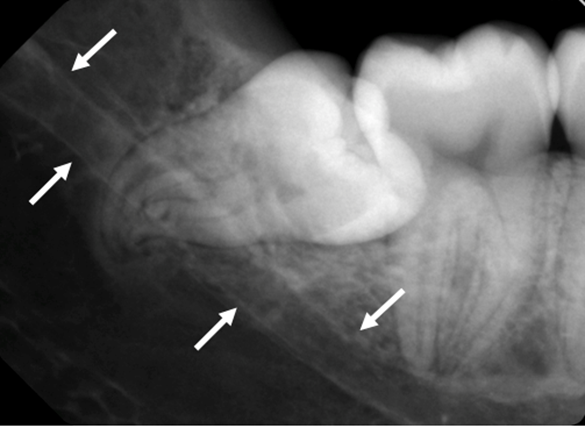

Mandibularkanalen (Figur 1) är lokaliserad i corpus mandibulae och sträcker sig fram till foramen mentale (3). Relationen mellan mandibularkanalen och rötterna på underkäkens tänder varierar. Det kan finnas allt ifrån en nära relation till ingen kontakt alls (4).